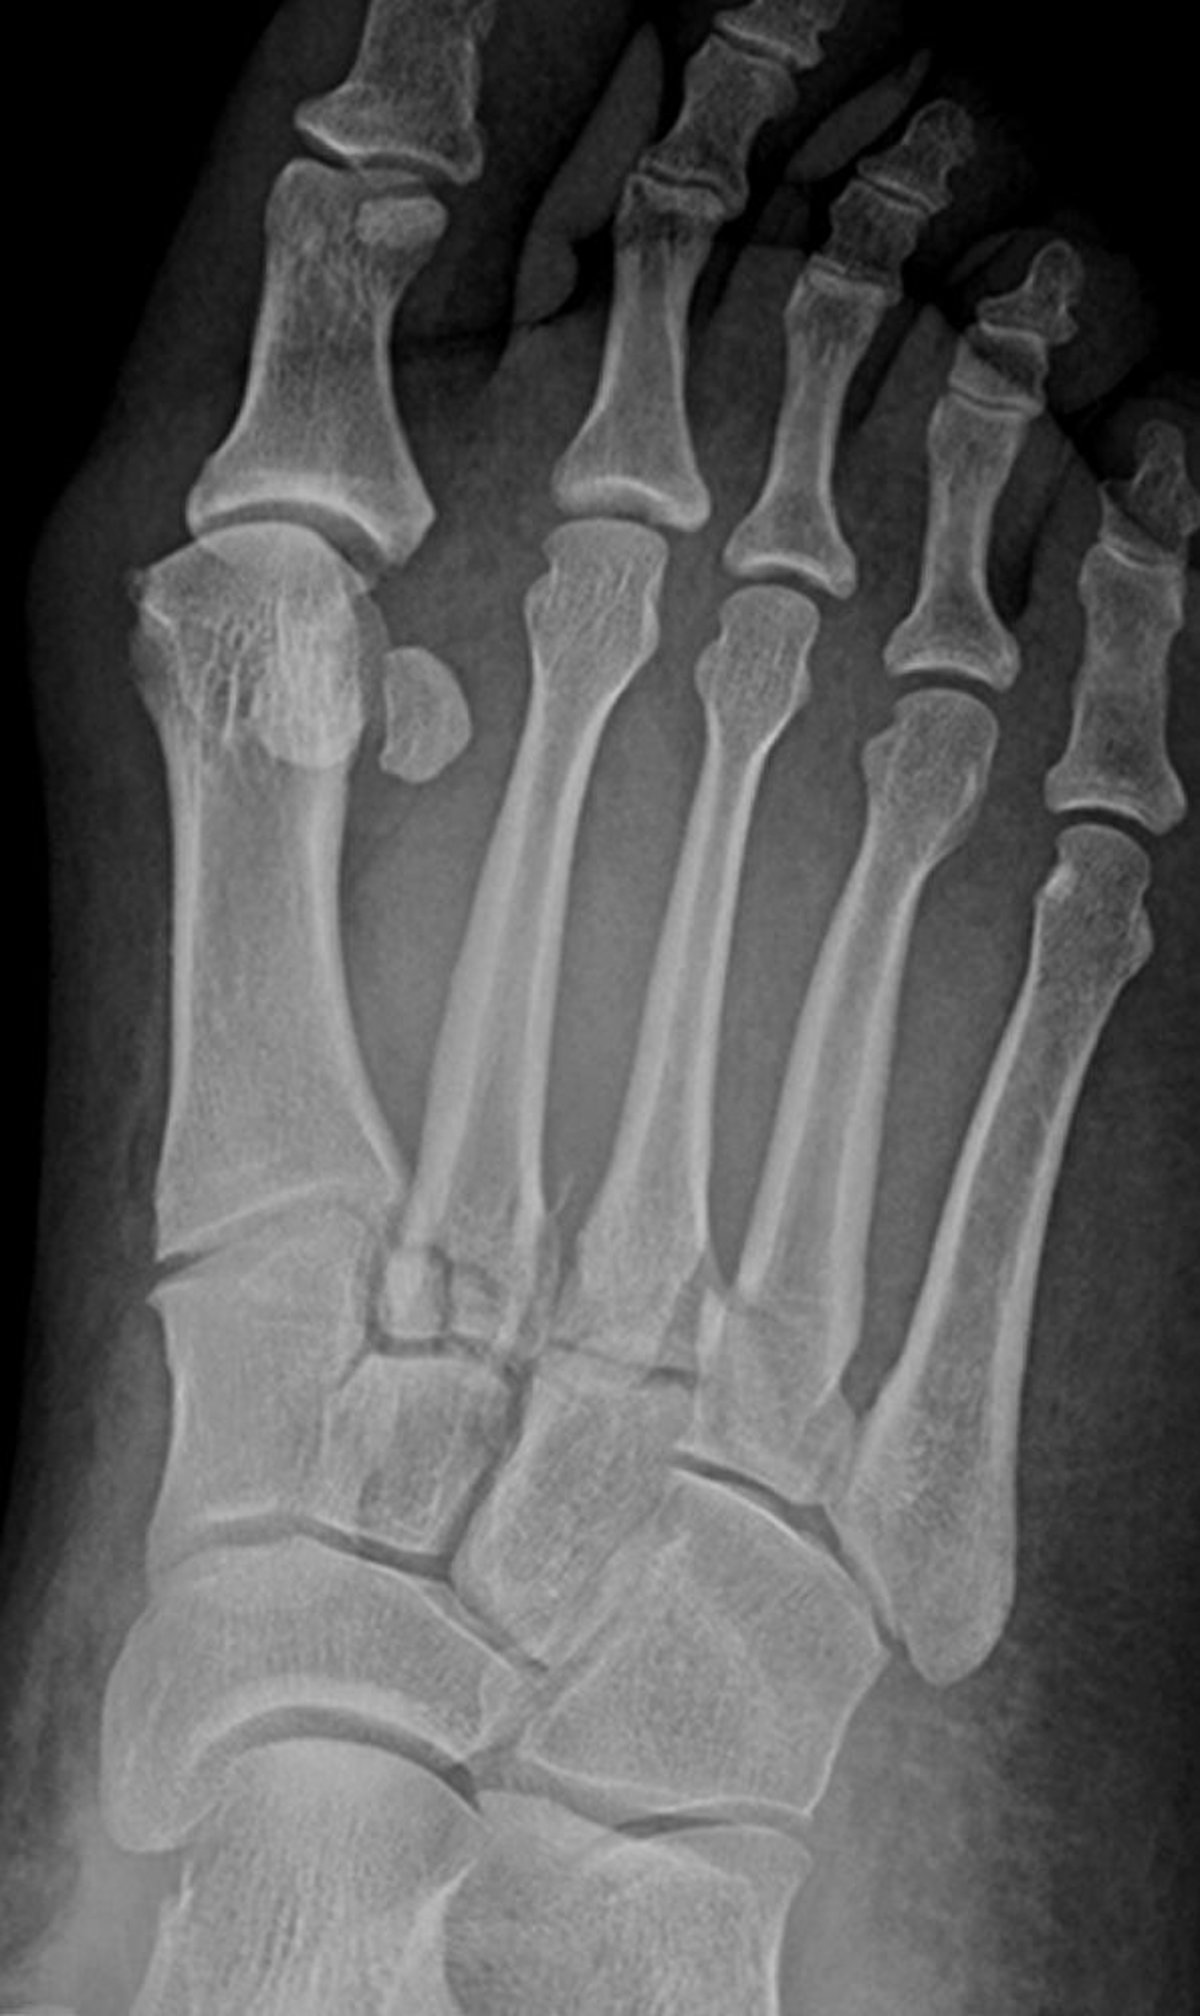

Fracturas de Lisfranc

Esta radiografía muestra fracturas en la base del segundo, tercero y cuarto metatarsianos. Las articulaciones tarsometatarsianas también están afectadas.